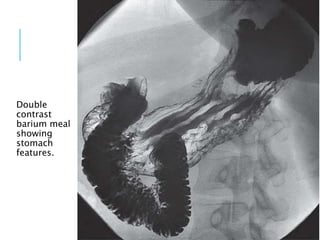

Double

contrast

barium meal

showing

stomach

features.